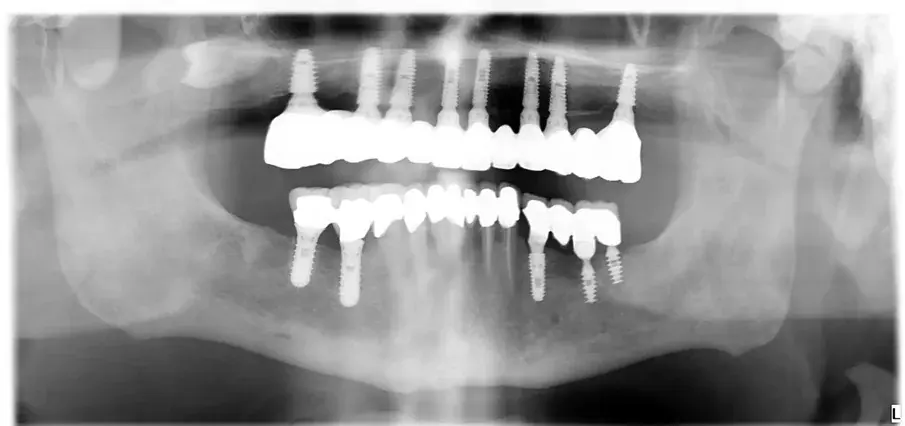

При последната среща беше поставена окончателната хибридна винтово-фиксирана протеза. Окончателната протеза се състоеше от CAD/CAM титанова рамка, завинтена към всички импланти, и три монолитни циркониеви протезни сегмента, залепени отгоре (фиг. 18а–в). Беше оценена оклузията и пациентът беше включен в четиримесечна програма за поддържане. При последната контролна визита (една година след поставянето на имплантите) всички импланти бяха успешни и пациентът беше удовлетворен от новата протеза (фиг. 19–22).

Фиг. 22: Едногодишна панорамна томография на зъбите.